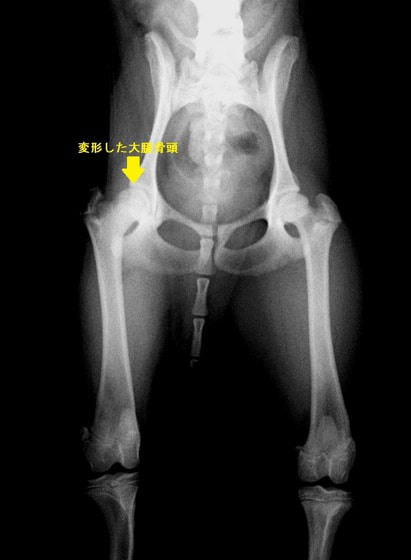

重度股関節形成不全の症例

ボール遊びの後の後肢の跛行を主訴に来院されました。院内ではモンローウォーク(腰を振って歩く歩様)が認められました。レントゲン検査において、左右股関節の形成不全および比較的重度の関節炎所見を認めました。左右ともに長期に及ぶ骨関節炎の進行により、寛骨臼に重度の骨変形・骨硬化が認められました。このような症例においては、THRのカップの定着が悪くTHRの手術の成功率が下がるため、機能回復の面では劣りますが、症状がより重く、筋肉の萎縮の認められた右後肢の大腿骨頭・骨頚切除術を実施しました。関節面に関節軟骨の欠損、骨増殖体を認めました。今後は、リハビリテーションを行い、患肢の機能回復に努め、反対側の大腿骨頭・骨頚切除術を検討していく予定です。

術前レントゲン

後肢の跛行を主訴に来院されました。レントゲン検査にて、左右股関節の形成不全および重度の関節炎所見を認めました。THRに関しては適応年齢(約9カ月齢以降)の範囲にありますが、左右とも長期に及ぶ骨関節炎の進行により、大腿骨頭・寛骨臼ともに重度の骨変形を伴っていました。このような症例において、THRのカップの定着が悪くTHRの手術の成功率が下がるため、機能回復の面では劣りますが、症状がより重いと判断された左後肢の大腿骨頭・骨頚切除術を実施しました。今後は、リハビリテーションを行い、患肢の機能回復に努めると共に、反対側の大腿骨頭・骨頚切除術を検討していく予定です。